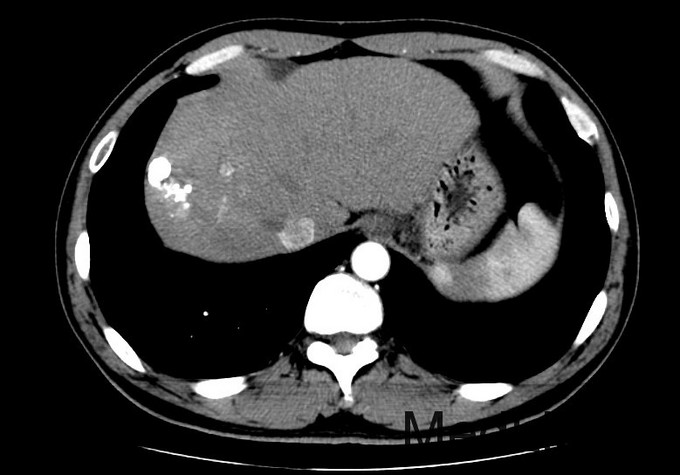

查体:血压131/76mmHg.神志清晰。颜色正常,无皮疹及瘀点。无肝掌。浅表淋巴结未触及肿大。眼睑无水肿,巩膜无黄染,结膜正常。双侧瞳孔等大正圆。心肺听诊无异常。腹型平坦,无腹壁静脉曲张,未见胃肠型及蠕动波,无瘢痕,脐部正常。腹软,无压痛及反跳痛,无腹肌紧张,未触及包块。肝未触及,Murphy征阴性,脾未触及,无触痛,肾未触及。无肝区叩击痛,肝上界位于右锁中线第6肋间,无肾区叩击痛,无脾区叩击痛。移动性浊音阴性。四肢活动自如,无双下肢水肿。扑翼样震颤阴性。 化验:血细胞分析:白细胞计数 3.9 10^9/L、血小板计数 121.0 10^9/L、血红蛋白 134 g/L,肝功酶谱:丙氨酸氨基转移酶 50 U/L、总蛋白 73.5 g/L、白蛋白 42.4 g/L、总胆红素 13.3 umol/L,凝血五项:凝血酶原百分活动度 76.4 %,丙肝抗体 27.90 S/CO,丙肝病毒RNA定量 <1.0E+03 IU/ml,甲胎蛋白 1296.00 ng/mL, 肝脏增强CT示:肝硬化,脾大,腹水少量。肝癌介入手术治疗后,S8段强化灶。肝右叶灌注异常,考虑门脉右前支受侵。

诊断:1丙肝肝硬化 活动期 代偿期 HCC术后 2高血压 治疗:入院后休息,低脂低盐软食。肿瘤辅助治疗,静点苦参碱。抗病毒,口服daclatasvir和sofosbuvir联合利巴韦林。控制血压,口服替米沙坦抗纤维化。对于S8段强化灶,考虑疾病进展,再行TACE治疗。

术后:查体:眼睑无水肿,巩膜无黄染。心肺听诊无异常。腹软,无压痛及反跳痛,无腹肌紧张,未触及包块。肝未触及,Murphy征阴性,脾未触及,无触痛,肾未触及。无肝区叩击痛,无肾区叩击痛,无脾区叩击痛。移动性浊音阴性。 化验:血细胞分析:白细胞计数 8.8 10^9/L、红细胞计数 4.04 10^12/L、血小板计数 113.0 10^9/L、血红蛋白 131 g/L、中性粒细胞百分比 88.4 %,肝功酶谱:丙氨酸氨基转移酶 258 U/L、天门冬氨酸氨基转移酶 245 U/L、白蛋白 34.1 g/L、总胆红素 29.4 umol/L,凝血五项:凝血酶原时间 12.2 秒,C反应蛋白测定:C反应蛋白 1.50 mg/L,降钙素原检测:降钙素原测定 0.08 ng/ml,甲胎蛋白测定:甲胎蛋白 1294.00 ng/mL。 患者6周前行一次TACE治疗,本次为病情进展,提示我们TACE术后必须加强随访,定期复查CT。